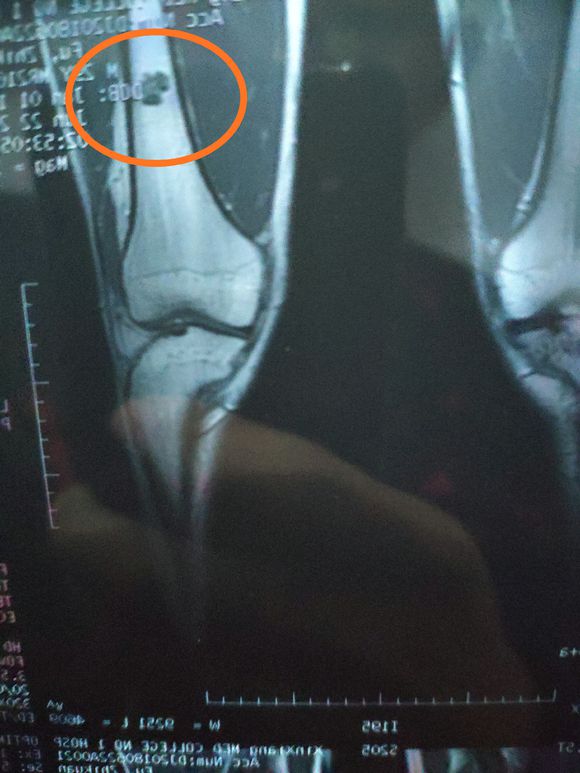

金色麦田 02019-07-10 患者2006年做了病灶刮除植骨+内固定术,2007年的时候做了股骨内固定拆除、植骨融合术,2009年的时候发现复发了,就做了...